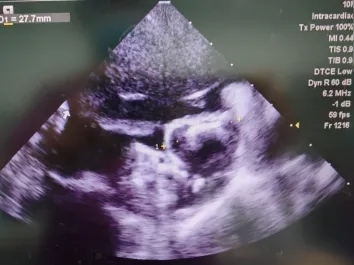

术中ICE复测缺损

ICE下心耳开口略低于左上肺静脉开口,属于低位心耳;

-

ICE Y轴模拟食道超声90°下心耳开口25mm,深度21.2mm;

ICE X轴模拟食道超声45°下开口27.2mm,深度24.8mm。

ICE多角度测量显示心耳开口径线存在显著差异,据此推断其开口横截面为椭圆形,而非圆形,塞式封堵器可利用口部椭圆的特性获得径向支撑。